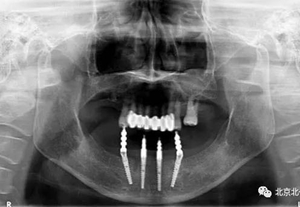

圖十五:術(shù)后即刻拍X片

圖二十一:半年后復(fù)查X片

圖二十二:2015年到2016年復(fù)查時(shí)X片 ,有圖有真相

圖二十四:2017年11月復(fù)查時(shí)照片,植體很穩(wěn)定, 無骨吸收。